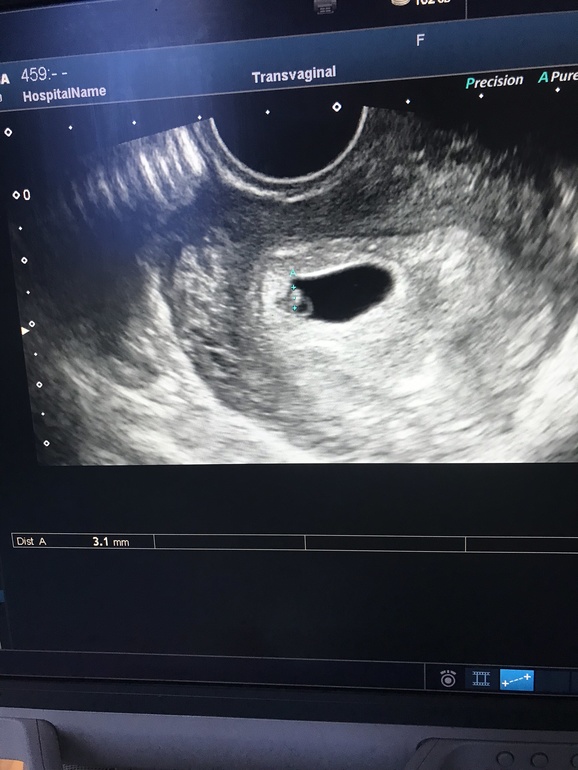

Кстати, что там метод Рамзи говорит? Мальчики слева, девочки справа, или наоборот? 🤣

Надо же, вроде справа, как на девочку?)

Сын вот слева обитал на таком сроке

Тихонечко вас поздравляю 💐💐💐💕💕💕🥳🥳🥳, посмотрела в другом посте, все правильно мальчик слева, девочка с права🥰

Спасибо ) ну да, смотрю фото сына на таком сроке - он слева был. Посмотрим, правда ли девчонка сейчас )